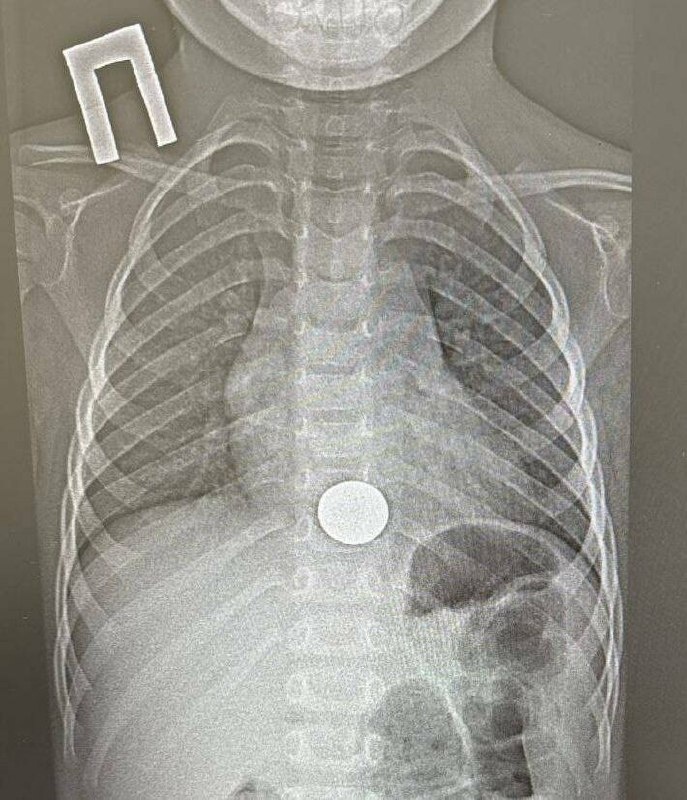

πŸ€πŸ©»Π’ НиТнСкамскС Π²Ρ€Π°Ρ‡ΠΈ дСтской Ρ€Π°ΠΉΠΎΠ½Π½ΠΎΠΉ Π±ΠΎΠ»ΡŒΠ½ΠΈΡ†Ρ‹ ΠΈΠ·Π²Π»Π΅ΠΊΠ»ΠΈ ΠΌΠΎΠ½Π΅Ρ‚Ρƒ ΠΈΠ· ΠΏΠΈΡ‰Π΅Π²ΠΎΠ΄Π° Ρ€Π΅Π±Π΅Π½ΠΊΠ°

ДСтский Ρ…ΠΈΡ€ΡƒΡ€Π³, Π²Ρ€Π°Ρ‡-эндоскопист Π˜Π³ΠΎΡ€ΡŒ Π¨ΠΎΠ³ΠΎΡ€ΠΎΠ² ΡƒΠ΄Π°Π»ΠΈΠ» ΠΈΠ½ΠΎΡ€ΠΎΠ΄Π½ΠΎΠ΅ Ρ‚Π΅Π»ΠΎ с ΠΏΠΎΠΌΠΎΡ‰ΡŒΡŽ эндоскопа. ΠœΠ°Π½ΠΈΠΏΡƒΠ»ΡΡ†ΠΈΡ заняла ΠΎΠΊΠΎΠ»ΠΎ ΠΌΠΈΠ½ΡƒΡ‚Ρ‹.

ПослС ΠΏΡ€ΠΎΡ†Π΅Π΄ΡƒΡ€Ρ‹ Ρ€Π΅Π±Π΅Π½ΠΊΠ° для наблюдСния ΠΏΠ΅Ρ€Π΅Π²Π΅Π»ΠΈ Π² хирургичСскоС ΠΎΡ‚Π΄Π΅Π»Π΅Π½ΠΈΠ΅, Π° ΡƒΠΆΠ΅ Π½Π° ΡΠ»Π΅Π΄ΡƒΡŽΡ‰ΠΈΠΉ дСнь, ΡƒΠ±Π΅Π΄ΠΈΠ²ΡˆΠΈΡΡŒ Π² Π΅Π³ΠΎ ΡƒΠ΄ΠΎΠ²Π»Π΅Ρ‚Π²ΠΎΡ€ΠΈΡ‚Π΅Π»ΡŒΠ½ΠΎΠΌ состоянии, выписали.